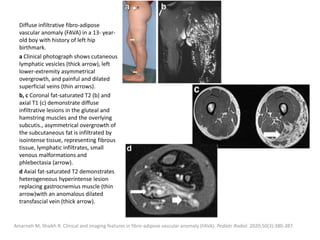

enhancement of the lesion

(*) and early venous

shunting (arrows).

Note the absence of

dilated arteries and

draining veins.

Flors L, Leiva-Salinas C, Maged IM, et al. MR imaging of soft-tissue vascular malformations: diagnosis, classification, and therapy

follow-up. Radiographics. 2011;31(5):1321-1341.

4-Year-old male with mixed

venous-lymphatic malformation.